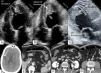

The echocardiogram showed moderate left ventricular (LV) systolic impairment and a massive mobile thrombus in the LV apex (Figure 1A and B) and another in the left atrium (Figure 1C).

(A) Transthoracic echocardiogram, apical 4-chamber view in diastole, showing apical LV thrombus; (B) transthoracic echocardiogram, apical 4-chamber view in systole, showing the thrombus protruding into the LV cavity; (C) transthoracic echocardiogram, apical 3-chamber view, showing the LV and LA thrombi; (D) cerebral computed tomography, displaying a large cerebral infarct; (E–G) abdominal computed tomography with contrast, showing splenic (E) and renal (F) infarcts and almost total occlusion of the infrarenal abdominal aorta (G). LA: left atrial; LV: left ventricular.

Computed tomography confirmed multiple cerebral (Figure 1D), splenic (Figure 1E) and renal (Figure 1F) infarcts, as well as an almost total occlusion of the infrarenal abdominal aorta (Figure 1G), distal to the origin of the inferior mesenteric artery.